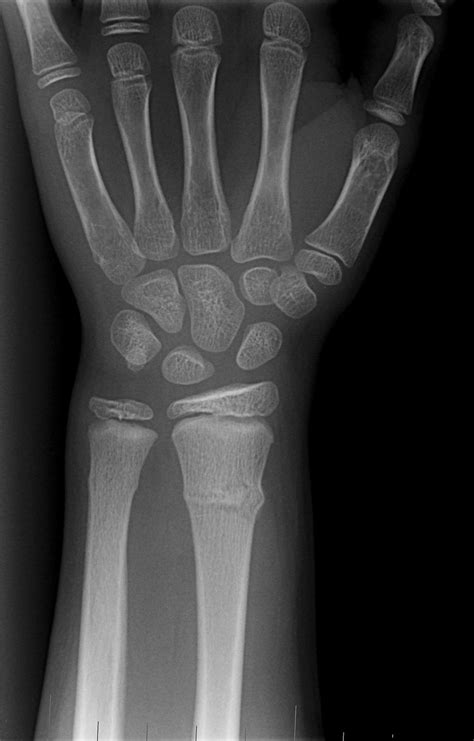

X Rays Of Broken Wrist Wrist Fracture Surgery | OrthoVirginia is a high-quality image in the Cleve collection, available at 1150 × 1800 pixels resolution — ideal for both digital and print use.

Recovering from a fracture broken wrist requires proper diagnosis and care. Learn about common wrist fracture symptoms, effective treatment options—including casting and surgery—and essential rehabilitation exercises to restore strength. Understand the healing timeline for distal radius fractures and discover expert tips to manage pain and ensure a smooth recovery process for your injured wrist.